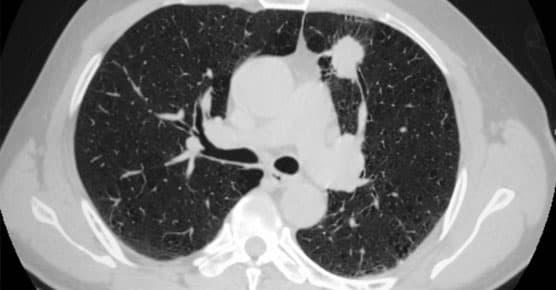

Screening

When lung cancer is detected early, treatment can begin sooner, giving patients a higher chance of success. We use advanced tools and techniques to screen and monitor people at high risk of developing cancer. Low-dose CT scans are quick and painless diagnostic tests for detecting very small changes in the lungs that could indicate cancer.